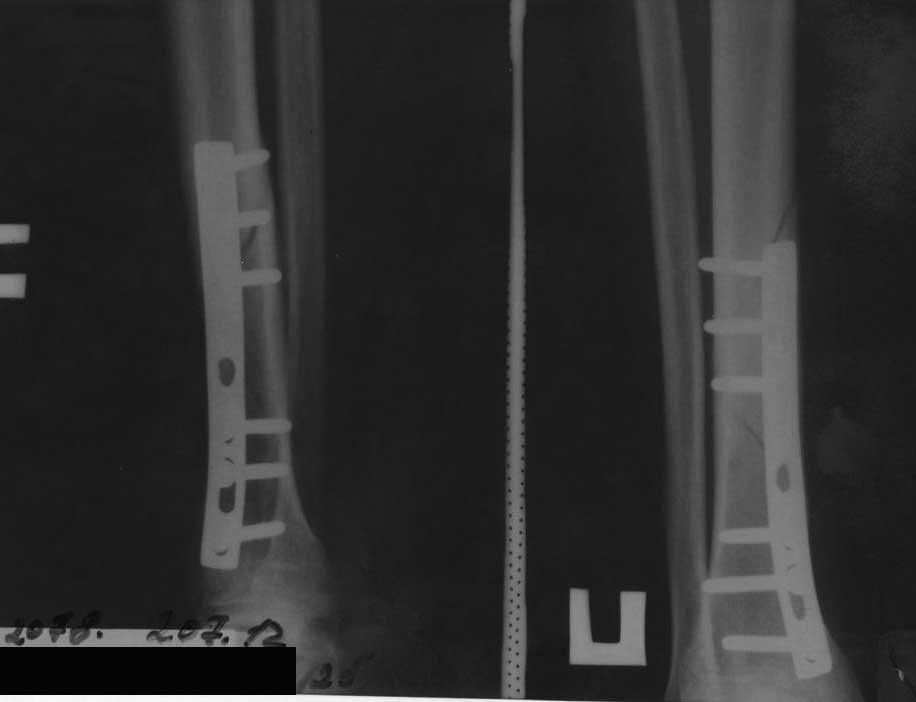

Больной 25 лет, нормостеник, курящий. Травма бытовая 28.01.2012.

Госпитализирован в травм. отделение. 30.01.2012 выполнено оперативное

вмешательство - открытая репозиция, металлоостеосинтез накостной пластиной

(сразу приношу извинения за качество п/о рентгенограмм, к тому же, у

больного сохранился

снимок только в прямой проекции). П/о период без особенностей. Выписан на

амбулаторное лечение. Через 4 месяца - полная нагрузка на ногу, вёл обычный

образ жизни. 02.07.2012 спрыгнул с дерева и внезапно почувствовал сильную

боль в голени. На рентгенограмме - повторный перелом. Временно наложен

сапожок HM Cast. Вопрос: что делать? Оставить так как есть? Открыться и

поставить пластину подлиннее(на б/б стержень у больного нет $)? По-моему,

линия излома проходит через места выхода винтов, боюсь, как бы они не стали

"распоркой" для костных отломков и не стали препятствовать сращению...